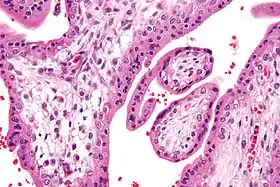

![]() صورة مجهرية تظهر الزغابات المشيمية. تكبير عالي جداً. صبغة الهيماتوكسيلين والأيوزين. صورة مجهرية تظهر الزغابات المشيمية. تكبير عالي جداً. صبغة الهيماتوكسيلين والأيوزين. | |